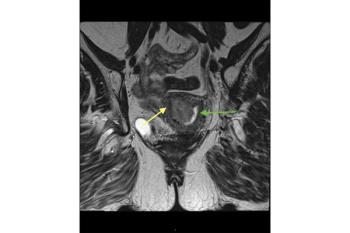

MRI scoring system for adnexal masses

O-RADS-MRI (ovarian-adnexal reporting data system magnetic resonance imaging) was previously tested in a retrospective single-center study. The new research was done prospectively in a much larger cohort and the findings, according to the authors, support publication of Version 1 of O-RADS-MRI.

The cohort underwent routine pelvic MRI for characterization of a sonographically indeterminate adnexal mass, according to routine diagnostic practice at the centers. The O-RADS-MRI score was prospectively applied by two onsite readers and one reader and one reader masked to clinical and ultrasonography data. Scoring was on a 5-point scale, with categories reflecting the positive likelihood ratio for malignant neoplasm.

In the earlier retrospective study, a diagnostic score of 2 was associated with a less than 2% risk of malignancy, whereas a score of 4 or higher had sensitivity and specificity for malignancy of 93.5% and 96.6%, respectively. The system was designed to relay the radiologist’s suspicions to the clinician and help standardize reporting of MRI imaging findings.